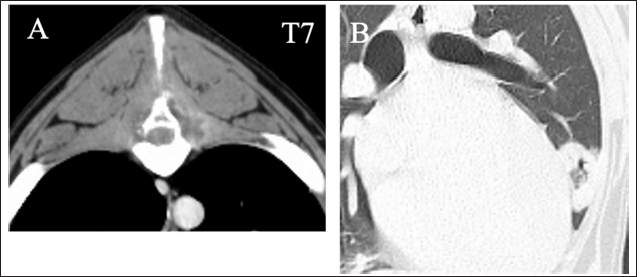

Computed tomography (CT) and magnetic resonance imaging (MRI) were conducted under general anesthesia. CT images revealed bone lysis of spinous processes of T7 and T8. Enhanced media detected homogenous contrast around the spinous processes and vertebral body of T7 (Fig. 2A). A ring-shaped lesion surrounding the soft tissue of the lung fields was detected as the same as an X-ray in the right cranial lobe (Fig. 2B). On the T1-weighted MRI, strong homogenous contrast enhancement highlighted post-contrast sequences at the lesion of T7 spinous process. A slight enhancement was observed in the middle of the vertebral body of T7 (Fig. 3A and B). On T2-weighted MRI, the spinous processes of T6 to T8 were hyperintense, and the lesion infiltrated into the vertebral body of T7 and spinal cord (Fig. 3C). Specific abnormalities were not detected for the cervical part by either CT or MRI. With examinations on the first day, neither infection nor neoplasm could be identified. The dog was hospitalized at the owner’s request. Antibiotics, including Vibramycin (7 mg/kg BID, p.o) and clarithromycin (8.9 mg/kg BID, p.o), were given during the hospitalization.

Fig. 2. Transverse contrast CT images show the lysis of the spinous process of T7 (A). Enhanced media detected homogenous contrast around the spinous processes and the T7 vertebra. Transverse CT images show the round, thin-walled cavity in the right cranial lobe of lung fields (B).